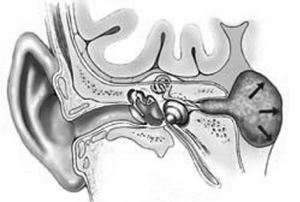

老年性聽力減弱的臨床表現

鼓膜正常,中年以後兩耳進行性對稱感音性聽力減弱,伴有高音耳鳴,先由3000Hz開始下降,逐漸波及4000~6000Hz中頻,亦可因基底膜破裂而高頻音突然喪失。一般談話中男人聲比女人和小兒語言易聽懂,純音測聽根據上述四種病理變化,可有平坦、下降等不同感音性聽力減弱曲線,語言識別率差,有音衰。